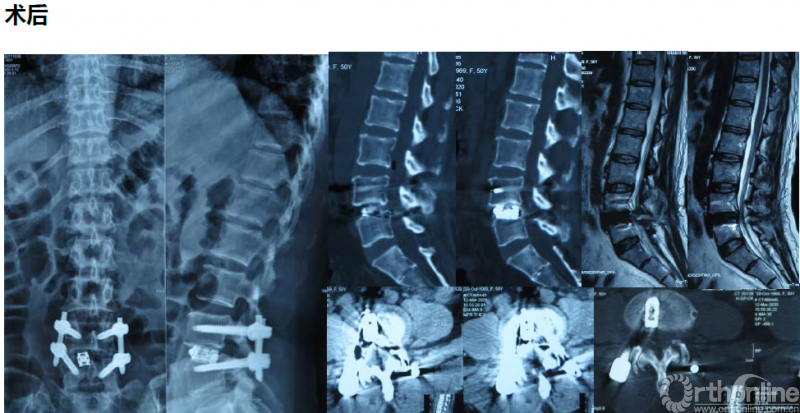

病例分享:(滑动查看)